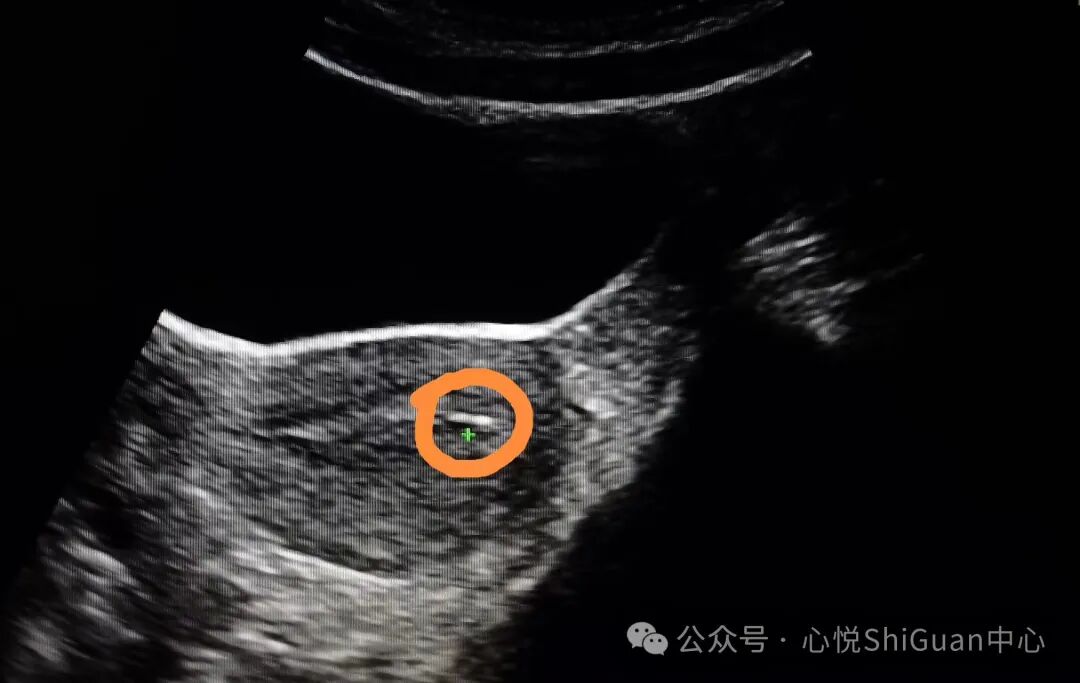

养囊就是把在体外培养到第3天的胚胎继续培养到第5~6天,此时的胚胎称为“囊胚”,而这个培养过程就叫养囊。

图片